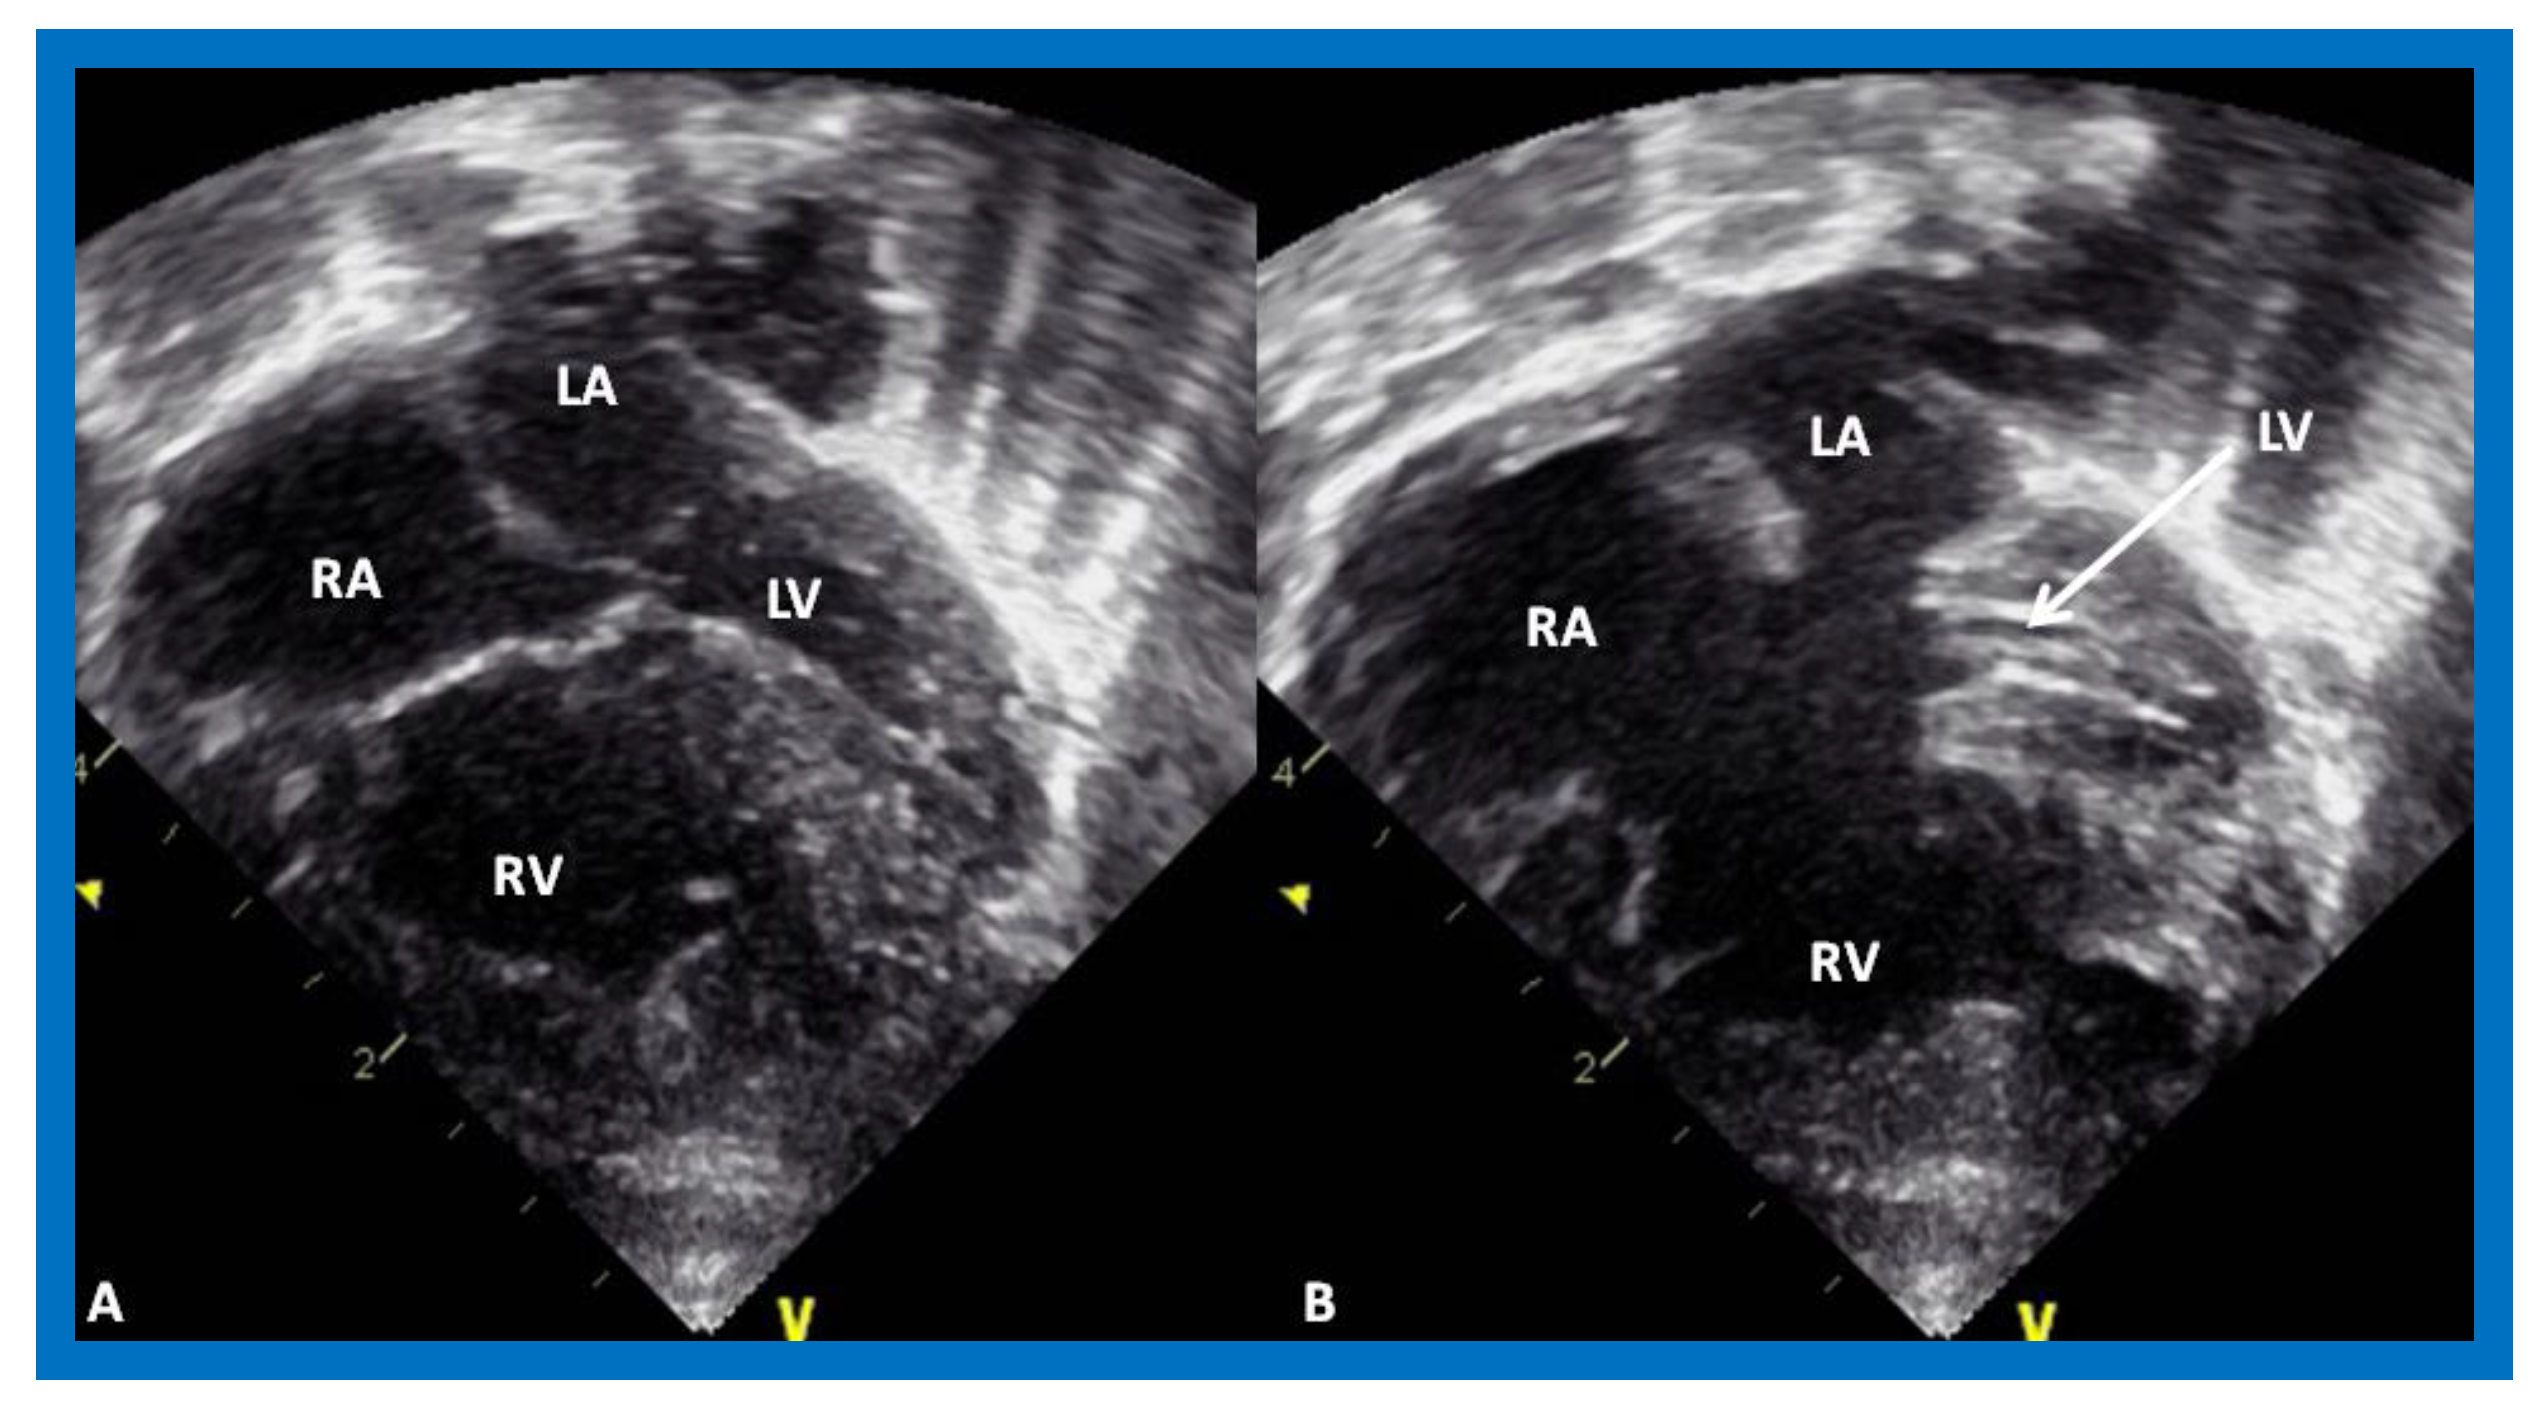

Figure 3.

Echocardiograms in apical four-chamber views of an infant with tricuspid atresia demonstrating a dilated left ventricle (LV), a small right ventricle (RV), and a dense band of echoes at the site where the tricuspid valve echo should be (ATV; thick arrow). Images with closed (A) and open (B) mitral valve are shown; the tricuspid valve remains closed in both situations. A ventricular septal defect (VSD; thin arrow) is also shown. LA, Left atrium; RA, Right atrium.